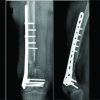

A 21-year-old male patient was involved in a traffic accident in April 2017, resulting in a Grade IIIB (Gustilo-Anderson Classification) exposed fracture of the left lower limb with soft tissue involvement and loss of the lateral compartment of the knee with a massive osteochondral defect. Initially, he was treated in another institution with a transarticular external fixator in extension, and the soft tissue defect was covered with a latissimus dorsi free flap and skin grafts in the leg. He developed graft necrosis, requiring multiple debridements. The defect was covered with an anterolateral right thigh-free flap and the edges with split-thickness skin grafts. At that moment, the patient refused a knee arthrodesis. Three months after the traumatic event, the patient was referred to our institution with moderate pain and purulent discharge from the proximal Schanz screws (Fig. 1). A two-stage surgical treatment approach was planned, including stage 1: eradication of infection and recovery of joint function and stage 2: transplantation with bipolar FOCA. Stage 1 started with the removal of the transarticular external fixator and debridement with femur and tibia sequestrectomy. Cultures were taken, and knee mobilization was performed; the defect was filled with polymethylmethacrylate beads (PMMA) mixed with gentamicin plus vancomycin. Oxacillin-sensitive Staphylococcus aureus was isolated, and intravenous cefazolin was indicated for 6 weeks. A computerized axial tomography (CAT) scan with 3D mirror reconstruction of both knees was requested for surgical planning to make the cutting guides and cats of the femoral condyle and the external tibial plateau (Fig. 2). The measurements of the defect in the tibia were anteroposterior 6 cm, transverse 8 cm, length 8 cm, and in the femoral condyle: anteroposterior: 7.3 cm, transverse 8.5 cm, and length 6 cm. Eight days after the first surgery, the second stage 1 procedure was performed to improve joint mobility. In this surgery, the reconstruction of the lateral compartment was performed with PMMA bone cement spacers, which were designed based on the 3D anatomical models (Fig. 2d). Functional recovery was achieved with a Judet’s quadricepsplasty, achieving a knee range of motion (ROM) of 0–90° (Fig. 3). Post-operatively, continuous passive mobilization machine therapy was initiated for 5 days, and physical therapy focused on improving ROM and pain with proprioception and quadriceps strengthening exercises; the patient also received education for walking with crutches. Cultures taken during this second surgery were negative, and cefazolin was continued until the treatment was completed. Once stage 1 was completed, the process of searching for a fresh allograft compatible in size with the patient’s tomographic measurements began. Due to delays in the approval of the FOCA transplantation by the health insurance company, stage 2 was initiated 15 months after the accident (or 12 months after the last surgery). At that time, radiographic follow-up showed preserved joint relationships and decreased femorotibial joint space with the osteosynthesis material in situ, with no sign of reactivation of the infection (Fig. 4). Once the allograft was obtained, X-rays and CAT scans of the allograft were taken to 3D-print the cutting guides and obtain an anatomical coupling between the defect and the fresh allograft. Before starting reconstructive surgery with FOCA, the 3D models were sterilized and sealed. Digital planning and cutting guides were performed according to the 3D reconstruction in Fig. 2. The cement spacers in the femur and tibia, as well as all the osteosynthesis material, were removed, and with the help of cutting guides, the defect was regularized to maximize the articular congruence of the femoral condyle and the external tibial plate. Bone tunnels were made in the femur, tibia, and fibula for anatomical ligament reconstruction. The allograft was fixed with interferential screws and plates in the distal femur and proximal tibia under fluoroscopic visualization. Reconstruction of the posterolateral corner, including the lateral collateral ligament, the popliteofibular ligament, and the popliteus tendon, was performed using the technique described by Chang et al., [7] achieving adequate joint stability. As shown in Fig. 5 and 3D printing, surgical guides allowed an anatomical and congruent joint reconstruction of the articular surface. Since the first post-operative day, the rehabilitation process has begun with isometric quadriceps exercises, active/active-assisted ROM exercises, and gait training with partial load. On the 5th post-operative day, the patient left the institution with adequate pain control and a ROM of 0–40°. Post-operative radiographs showed recovery of joint congruency, alignment, and adequate fixation of the bipolar FOCA (Fig. 6). During follow-up, no complications were reported, and there were no signs of infection reactivation. At the last follow-up, 5 years after transplantation with FOCA, the patient reported no functional limitations (mobility, self-care, usual activities) or pain but reported moderate symptoms of anxiety or depression through the EQ-5D-3L questionnaire. Nevertheless, he rated his overall health status with a score of 90 on a scale of 0–100. The final ROM of the left knee was 0–90°, without functional instability. Fig. 7 shows the radiological follow-up at the last control. The patient provided consent for publication.